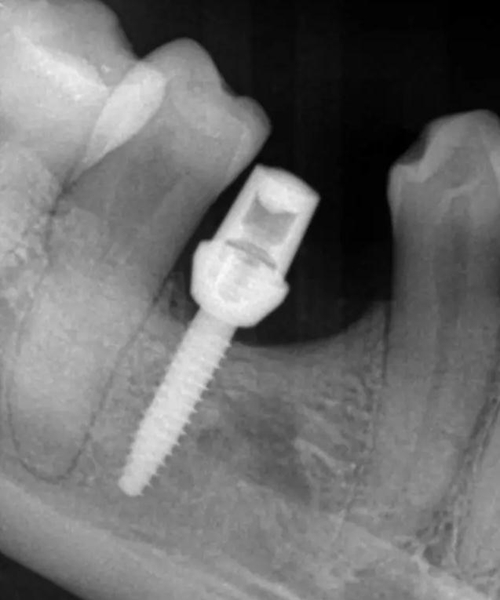

偏遠(yuǎn)中植入。 術(shù)后病人恢復(fù)良好, 無(wú)感覺異常。

三個(gè)月后上基臺(tái)